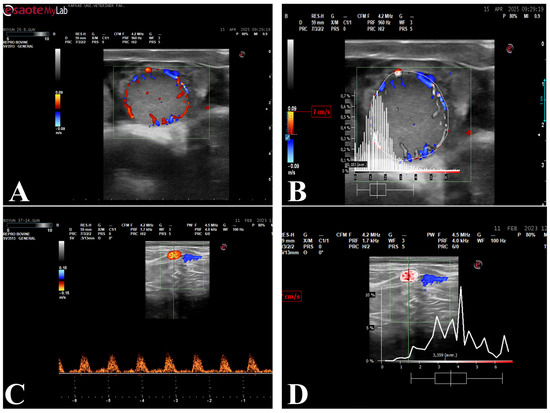

Figure 2.

Color Doppler ultrasonographic evaluation of the corpus luteum and spectral Doppler assessment of uterine artery blood flow. (A) Color Doppler illustrating luteal perfusion area; (B) Analysis of the perfusion area within the identified corpus luteum; (C) Spectral Doppler of the uterine artery; (D) Spectral Doppler waveform analysis obtained from the uterine artery.

2.6. Perfusion and Spectral Doppler Analysis

Perfusion of the corpus luteum and spectral Doppler analyses of the uterine artery were performed using PixelFlux (v. 18.03.11, Chameleon® Software, Münster, Germany) software. Corpus luteum perfusion area (CL-PA) and corpus luteum area (CL-A) were calculated based on the mean values obtained from three separate images. The three images were acquired consecutively during the same examination session, and frames representing the maximal cross-sectional area of the corpus luteum with clearly visible vascular signals were selected to ensure measurement consistency. Care was taken to avoid artifacts and frames with incomplete vascular visualization. From the spectral Doppler waveforms obtained from the uterine artery, maximum velocity, blood flow average velocity, blood flow volume, resistance index, uterine artery area and pulse rate were calculated. Measurements were performed on images containing three regular cardiac cycles (Figure 2).